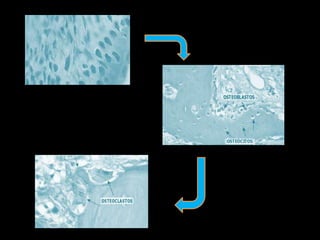

El documento describe el tejido óseo, incluyendo los tipos de células óseas como osteoblastos, osteoclastos y osteocitos. Explica que el hueso está en constante remodelación a través de la resorción por los osteoclastos y la formación por los osteoblastos. El proceso de remodelación ósea incluye las fases de activación, resorción, reposo, formación, mineralización y fase quiescente.